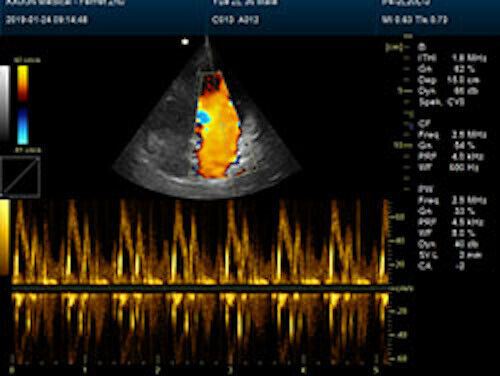

Large Animal Veterinary Color Doppler Ultrasound & Rectal Probe

| Powerful function & Configuration • Large screen display • Built-in lithium battery • Small size, light weight, easy to carry, N.W. ≤ 5kg • Equipped with a wide range of probes for abdominal, obstetric, vascular, cardiac, small organ, urinary applications • Built-in 4D module with optional 4D volume probe • A variety of digital peripheral interfaces, provides a variety of image output methods • PC platform, easy to operate, meet various software upgrades |

| Rich clinical application function • B+CF (Dual Images) • B+CF/PDI/DPDI+PW (Triplex) • Convex extended imaging technology • Linear array deflection/Trapezoidal imaging technology • Spatial compound Imaging technology • Panoramic imaging technology (optional) • 3D/4D imaging technology (optional) • Speckle noise removal technology • Pulse inversion tissue harmonic imaging technology (iTHI) |